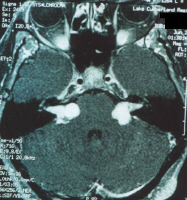

Refer to the picture above for question 3

3. Systemic associations include: